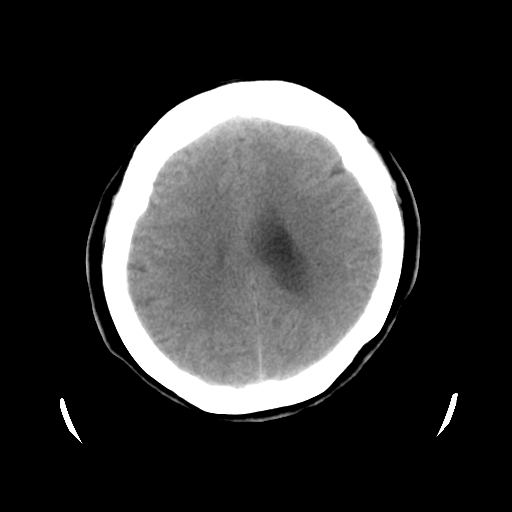

以下是引用cgf在2010-1-3 17:53:00的发言:[br]此病例多考虑:透明隔发育异常 透明隔囊肿可能性大;右侧基底节区(尾状核头)小片状低密度影考虑陈旧性腔梗[br][br]透明隔发育异常:包括透明隔间腔(第五脑室)、韦氏腔(第六脑室)、透明隔囊肿、透明隔缺如;前两者属于正常变异,后两者属于发育畸形;[br]透明隔间腔向下扩张形成韦氏腔;[br]有时透明隔间腔与透明隔囊肿很难鉴别;透明隔间腔间距一般不超过0.5cm,间距大于0.5cm时应考虑透明隔囊肿;[br]透明隔缺如为两侧脑室间隔缺如、融合成单脑室畸形,可伴有智力发育异常;[br][br]

以下是引用liaoqiang在2010-1-3 16:04:00的发言:[br]考虑侧脑室脉络丛囊肿?不除外变异的威氏腔。

以下是引用江广1996在2010-1-3 20:17:00的发言:[br]考虑变异的威氏腔。不除外侧脑室脉络丛囊肿.[br]透明隔囊肿大多数偏前,在侧脑室前角之间。